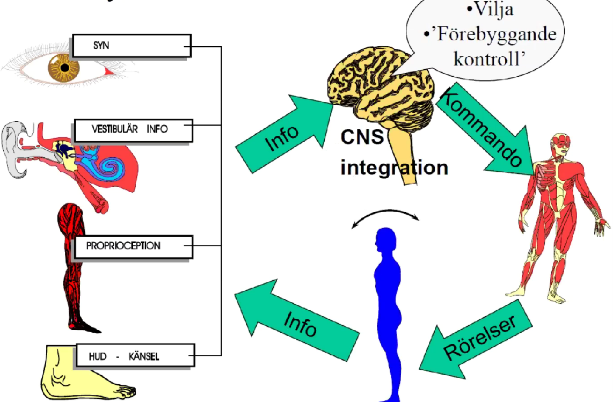

Beskriv översiktligt hur balanssystemet fungerar

- Syn, vestibulär info, proprioception och hudens känsel integreras i hjärnstammens vestibulariskärnor och har också hjälp av cerebellum, medvetandet kan påverka genom att vi vill stå stadigare eller slappna av mer

- Styrsignaler skickas sedan ut till muskler (ögonmuskler, nacken, ryggen, vadmuskler osv) och vi kan motta ny information från synen osv vilket ger nya kommandon

Vad orsakas yrsel av?

- Störningar i receptororganen

- Störningar i CNS

- Kombinationer

- Funktionell (upplevelse, avvikelse hittas inte)

- Fysiologisk (plant golv med sneda väggar)